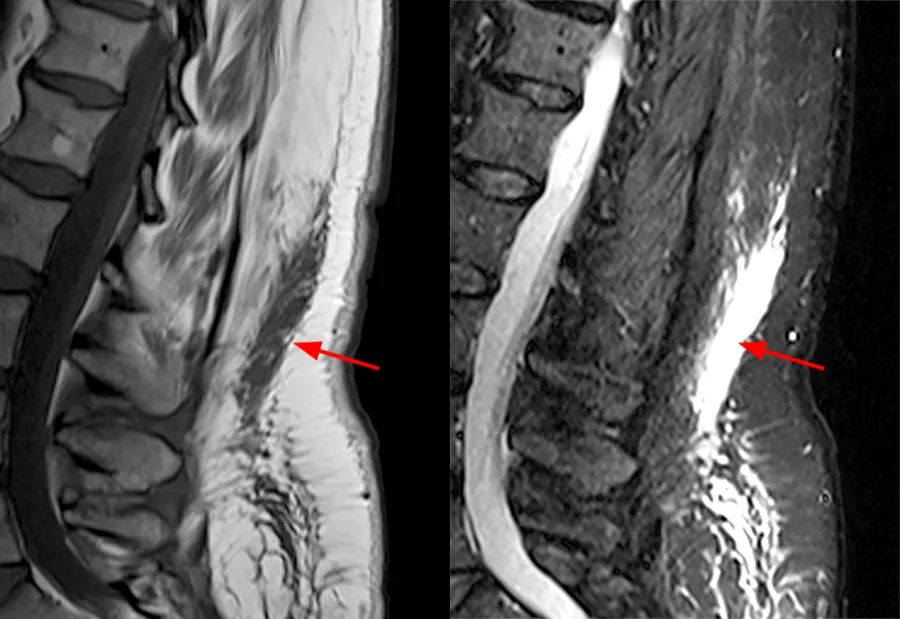

一例长期使用激素治疗的儿童,椎管内硬膜外脂肪明显增多,背侧脂肪前缘超过椎板前缘,脊髓受压呈 「 圆饼 」 状。

轴面上 T2WI 收到硬膜外脂肪的推挤,硬膜囊可以发生变形(正常为椭圆形)通常为多边形(A)、星状(B)或 Y 形或 V 形(C-D)